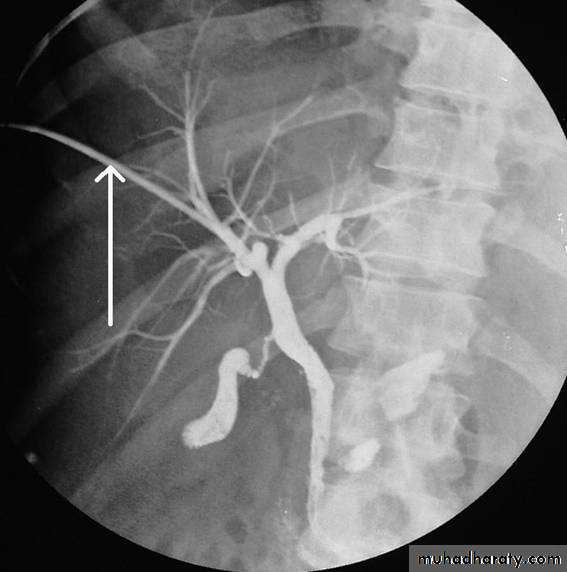

PTC

MRCP

• non-invasive

• no contrast.Gall stone & cholecystitis

Obstructive jaundice

ERCP & MRCP